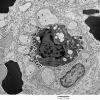

PERIPHERAL NEUROPATHY

5 AXONAL REGENERATION (3)